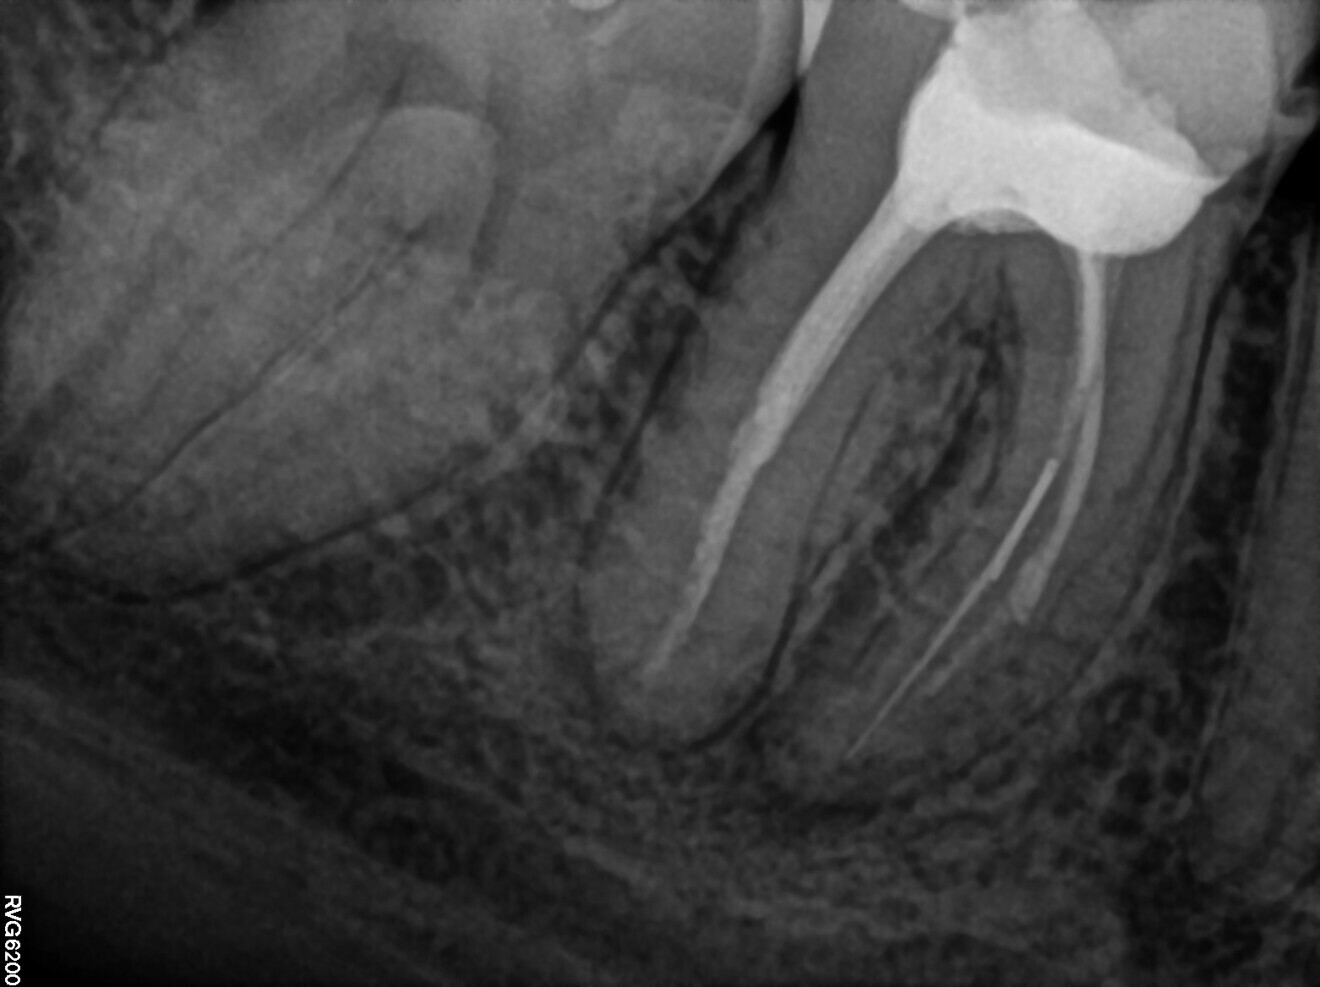

The patient came to the office because of moderate pain connected with the mandibular right first molar. A periapical radiograph and CBCT scan were performed. The images revealed radiolucency around the mesial root of the molar. Also, two pieces of a broken instrument were visible, one in the middle part of the root, before the curvature, and the other slightly below the curvature (Figs. 12 & 13).

After administering anaesthesia and placing a dental dam, the composite restoration was removed, and a temporary restoration with flowable composite and flowable dental dam for the root canal treatment was performed (Figs. 14–17). After removing the filling material from the mesiolingual and distal canals, access to the broken file was performed. The first piece of the instrument was removed with the ultrasonic tip (Fig. 18), and the tip of the second piece of the file then became visible. Unfortunately, the removed file piece broke in the middle and only the coronal part could be retrieved (Fig. 19). Because the apical part of the broken file was invisible and did not emerge from the canal during the irrigation and activation, an attempt at bypassing it was made. Analysis of the CBCT scan did not reveal a clear answer as to whether there was one apical foramen, so during the bypass procedure through the mesiolingual canal, a periapical radiograph was performed. The radiograph indicated that either there was a ledge in the apical area or there were two separate apical foramina (Fig. 20). For the irrigation protocol, the AutoSWEEPS mode was used at 1.2 W power with the flat SWEEPS 300/20 fibre tip. The tips of both mesial canals were placed below the orifice. The Less-Prep Endo protocol was performed twice in the manner described elsewhere.5 After the irrigation, irrigant flow between both canals was rapid.